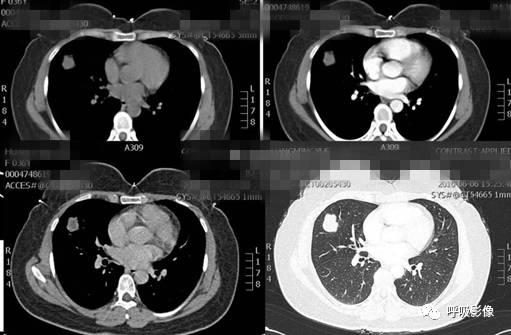

简单病史:女,35岁。查体发现肺部占位。胸部CT;右肺中叶外侧段近胸壁处圆形病变,边缘光滑,无毛刺, 增强扫描可见强化。

诊断: 肺良性肿瘤或孤立性转移瘤

诊断依据:青年女性,右肺中叶结节影,边缘光滑,密度均匀,无明显分叶、毛刺,临近胸膜无受累、肋骨无压迹,不符合肺恶性肿瘤诊断;患者无症状,不符合感染性疾病;病变密度均匀,内无坏死,无卫星灶,不符合结核球诊断。综合考虑肺良性肿瘤或孤立性转移瘤可能性大,病变位于胸膜下,孤立性转移瘤需考虑。病变增强扫描可见血管样强化,提示原发瘤血供丰富,最终病理为绒毛膜癌肺转移。